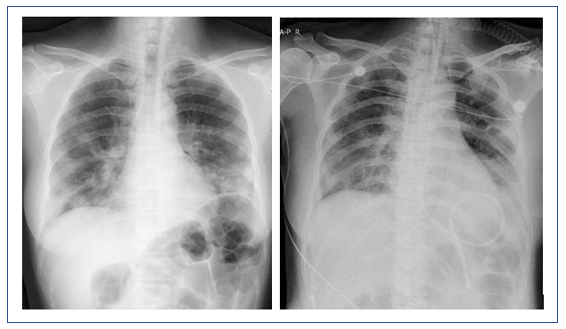

图4 患者治疗前后X线胸片对比

左:2018年12月31日胸片;右:2019年1月7日胸片

该患者的临床特点是D-二聚体水平持续性增高,需要注意下列问题:①追问病史,查找其他导致原因D-二聚体水平升高的原因。②患者X线胸片可见双下肺病变依然存在,上肺边缘和肋弓下仍有渗出,虽然个别区域病变有所吸收,但是整体并未明显好转,甚至双侧出现了少量胸腔积液,支气管管壁增厚,仍可见胸膜下三角形实变影,肺动脉增粗。因此还需考虑肺栓塞,应行CT肺动脉造影(CTPA)检查,用以解释D-二聚体水平升高的原因,另外除外肺栓塞。该患者各种病毒学检测均提示阴性,是否可以除外病毒感染?尽管患者免疫指标低,也可能与机体应激反应有关。如果排除病毒感染,接下来应考虑非感染性疾病可能。由于肺栓塞属于致死性疾病,建议通过CTPA检查首先排除这种可能。该患者目前不考虑肺水肿诊断,前述检查也不支持病毒性肺炎的诊断。插管后患者氧合有所改善,但病情仍然较重,肺内病变主要考虑肺实质(间质)病变、支气管病变和肺血管病变。所以逐渐聚焦到患者是否为肺血管病变,如肺血管炎或肺血栓。

经过治疗后,该患者的氧合有所改善,胸部CT提示肺部磨玻璃影明显吸收,但斑片状实变影愈加明显。此外,还出现了少量的胸腔积液。所以还是考虑患者有无潜在的血管炎或结缔组织疾病。由于患者的血管病变比较突出,D-二聚体和肿瘤标志物水平升高。所以暂时不能除外淋巴瘤或血管相关肿瘤。此时可以考虑行支气管肺泡灌洗,同时取标本送病理检查。

该患者经过短期治疗后,肺部磨玻璃影明显吸收。这种效果应是来源于糖皮质激素的作用。除了血管炎是否也要考虑皮肌炎的可能,可以做皮肌炎抗体检查。另外,建议患者行支气管肺泡灌洗和NGS检查。患者胸部CT显示双下肺背段有斑片影,这或许与患者机械通气时间长有关,可能为重力依赖区斑片渗出影。